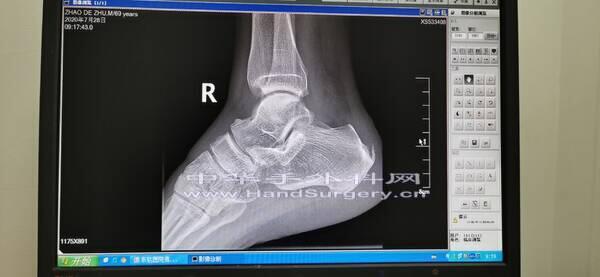

楼主| 发表于 2020-7-28 20:35:07 | 显示全部楼层

1.png